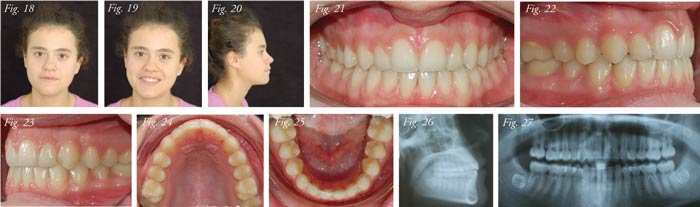

The first archwire positioned must be very resilient (0.012-

or 0.013-inch NiTi or CuNiTi) to ensure light forces and rapid

dental movements, and will remain in place for a period of five

to 16 weeks. If necessary, post-treatment finishing can be carried

out using a more rigid wire (0.016-inch NiTi or TMA beta-titanium)

(Figs. 4-27).